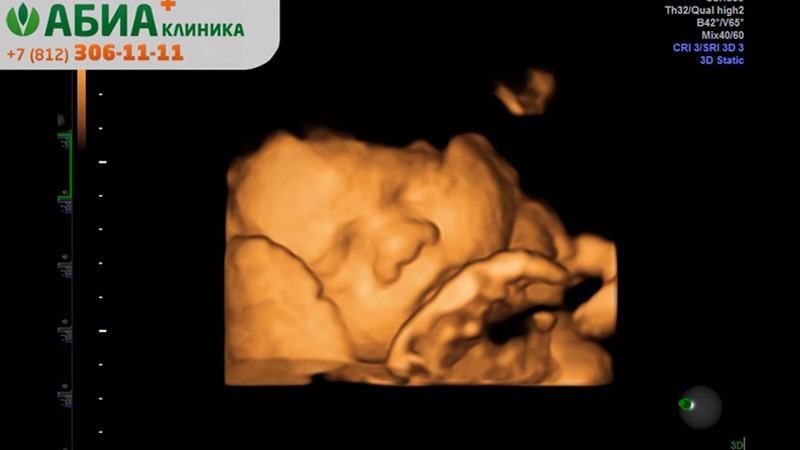

| Акция "Первая встреча в 3D/4D". В стоимость входит УЗИ плода в режиме 3D/4D, распечатка фотографии и запись видео на usb-носитель клиники | 4900 |